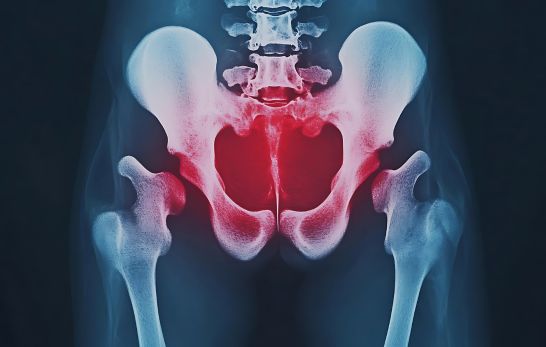

In dieser Kategorie konzentrieren wir uns auf Beckenverletzungen, Operationen, Schließmuskelschäden sowie Blasen- und Darmstörungen. Diese Themen sind eng mit der Lebensqualität verbunden, da sie oft Inkontinenz und andere Entleerungsstörungen verursachen können. Zudem beleuchten wir Fisteln im Darm- und Blasenbereich, ein komplexes Problem, das Beeinträchtigungen im Alltag mit sich bringt. Leser finden hier kompakte Einblicke in Ursachen, Symptome und Behandlungsmöglichkeiten dieser medizinischen Herausforderungen.

Die Behandlung von Beckenverletzungen und die Durchführung von Operationen im Beckenbereich sind komplexe medizinische Herausforderungen, die häufig mit schwerwiegenden Nachwirkungen einhergehen. Besonders die Inkontinenz (unfreiwilliger Harn- oder Stuhlverlust) und andere Entleerungsstörungen stehen oft im Fokus, da sie einen erheblichen Einfluss auf die Lebensqualität der Betroffenen haben. Dieser Artikel beleuchtet die genauen Zusammenhänge zwischen Beckenverletzungen, Operationen und der Entstehung von Inkontinenz und Entleerungsstörungen.